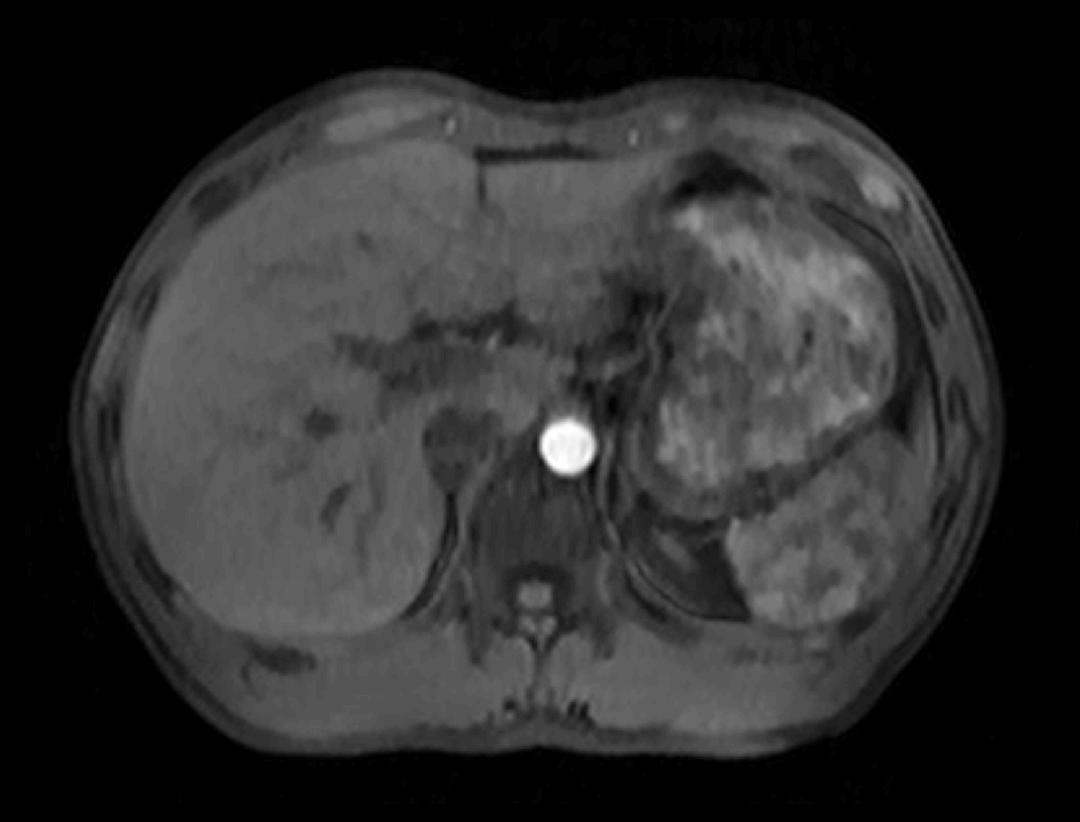

光梭®2.0成像应用于磁共振腹部动态增强扫描,可实现16倍采集加速,清晰捕捉组织信号连续动态变化,精准捕获腹部动态影像的每一瞬间,实时、全方位锁定病灶。

腹部